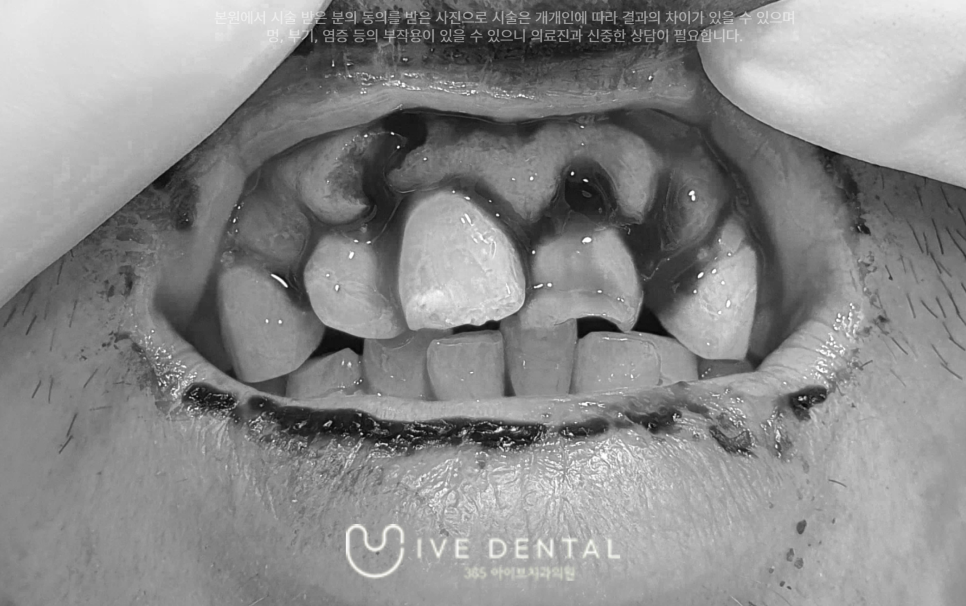

주말에 작업을 하시다가 사다리에서 넘어져 앞니 부위가 파절되신 환자분입니다.

한눈에 보기에도 심각한 상태인 분입니다.

앞니들이 다 파절되었으며 아예 뽑혀 나간 치아도 보이는데요.

잇몸의 손상도 심각한 상황입니다.